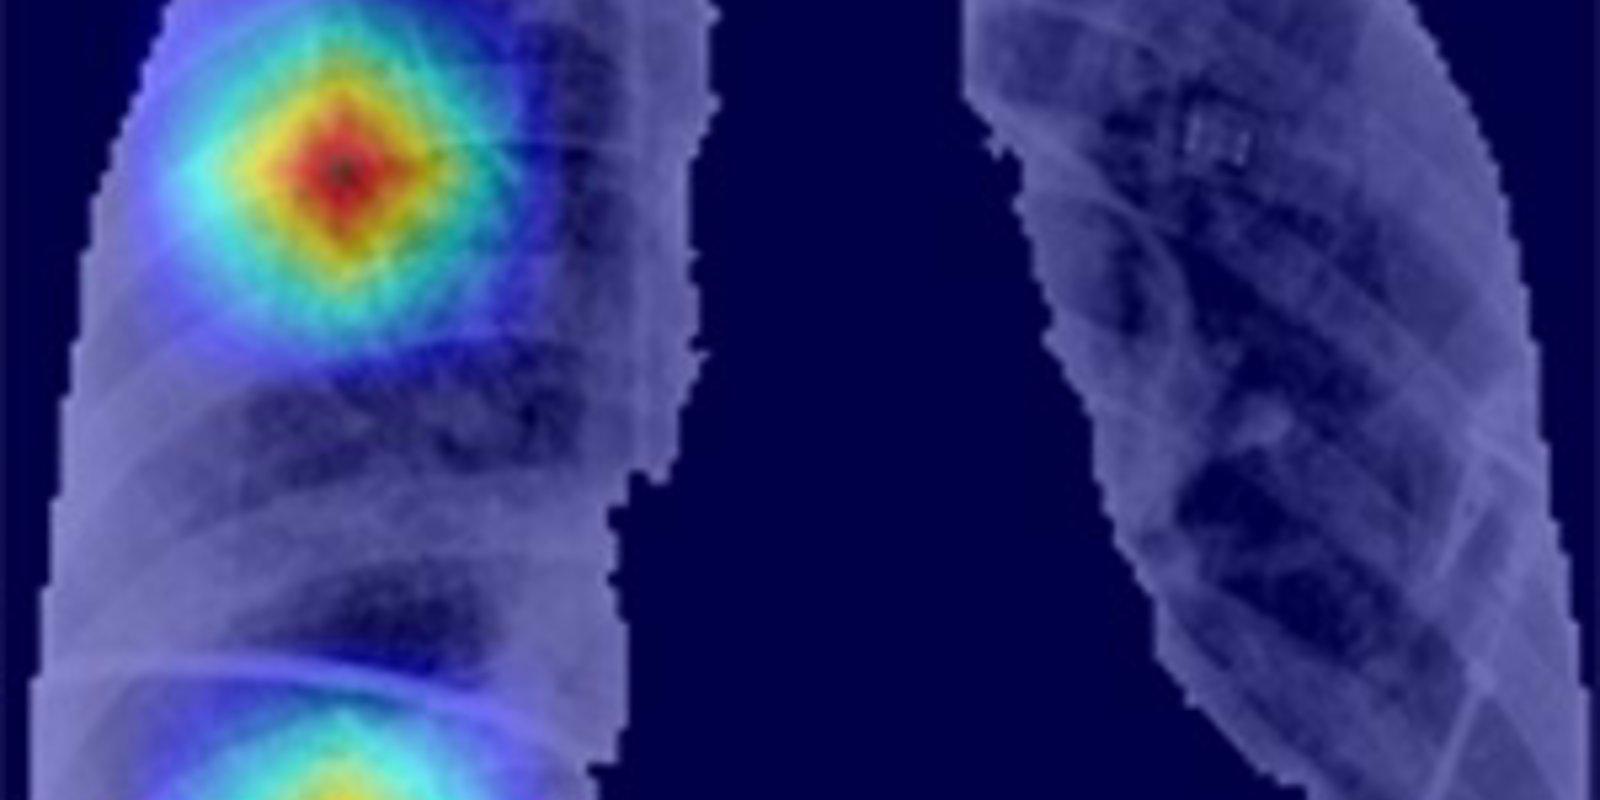

'CoronavIAruX' proporciona un método objetivo complementario, mínimamente invasivo para el diagnóstico, que evalúa el grado de afectación por la Covid-19. Alcanza una precisión por encima del 90 por ciento, superior incluso a la alcanzada por los expertos en radiología. Además, proporciona evidencias con capacidad diagnóstica en estadios incipientes de la enfermedad (los cinco primeros días).

La herramienta también identifica el área de mayor afectación y permite cuantificar de forma objetiva lo extenso de la infección, sin olvidar que reduce significativamente el tiempo dedicado por los expertos en radiología a la evaluación de cada paciente.